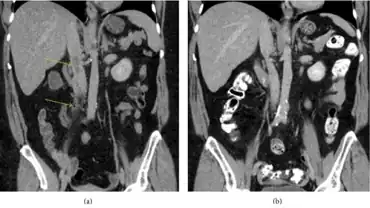

| a)Image findings are consistent with septic deep thrombophlebitis of proximal right ovarian vein b) 2.5 months later, complete resolution of septic thrombophlebitis | |